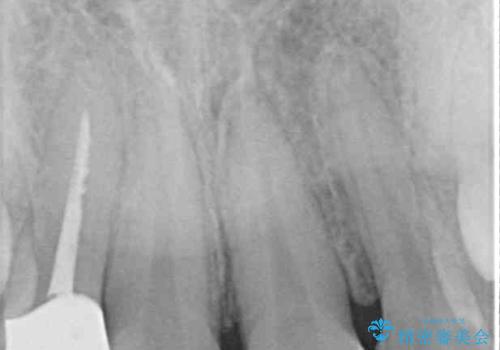

- 根管治療はやり直さずに、ファイバーポストを使用した土台を植立して、オールセラミッククラウンにて補綴することとしました。

神経を取り除いた歯の変色は、クリーニングやホワイトニングでは改善できないため、オールセラミッククラウンなどによる補綴治療が必要となります。